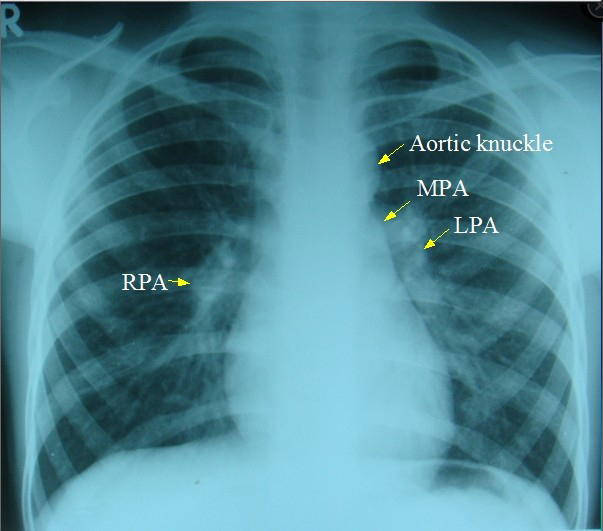

![A Day In The Life… [4]](https://tipsofspears.com/wp-content/uploads/2026/03/f8c7f-xray1.jpg?w=603)